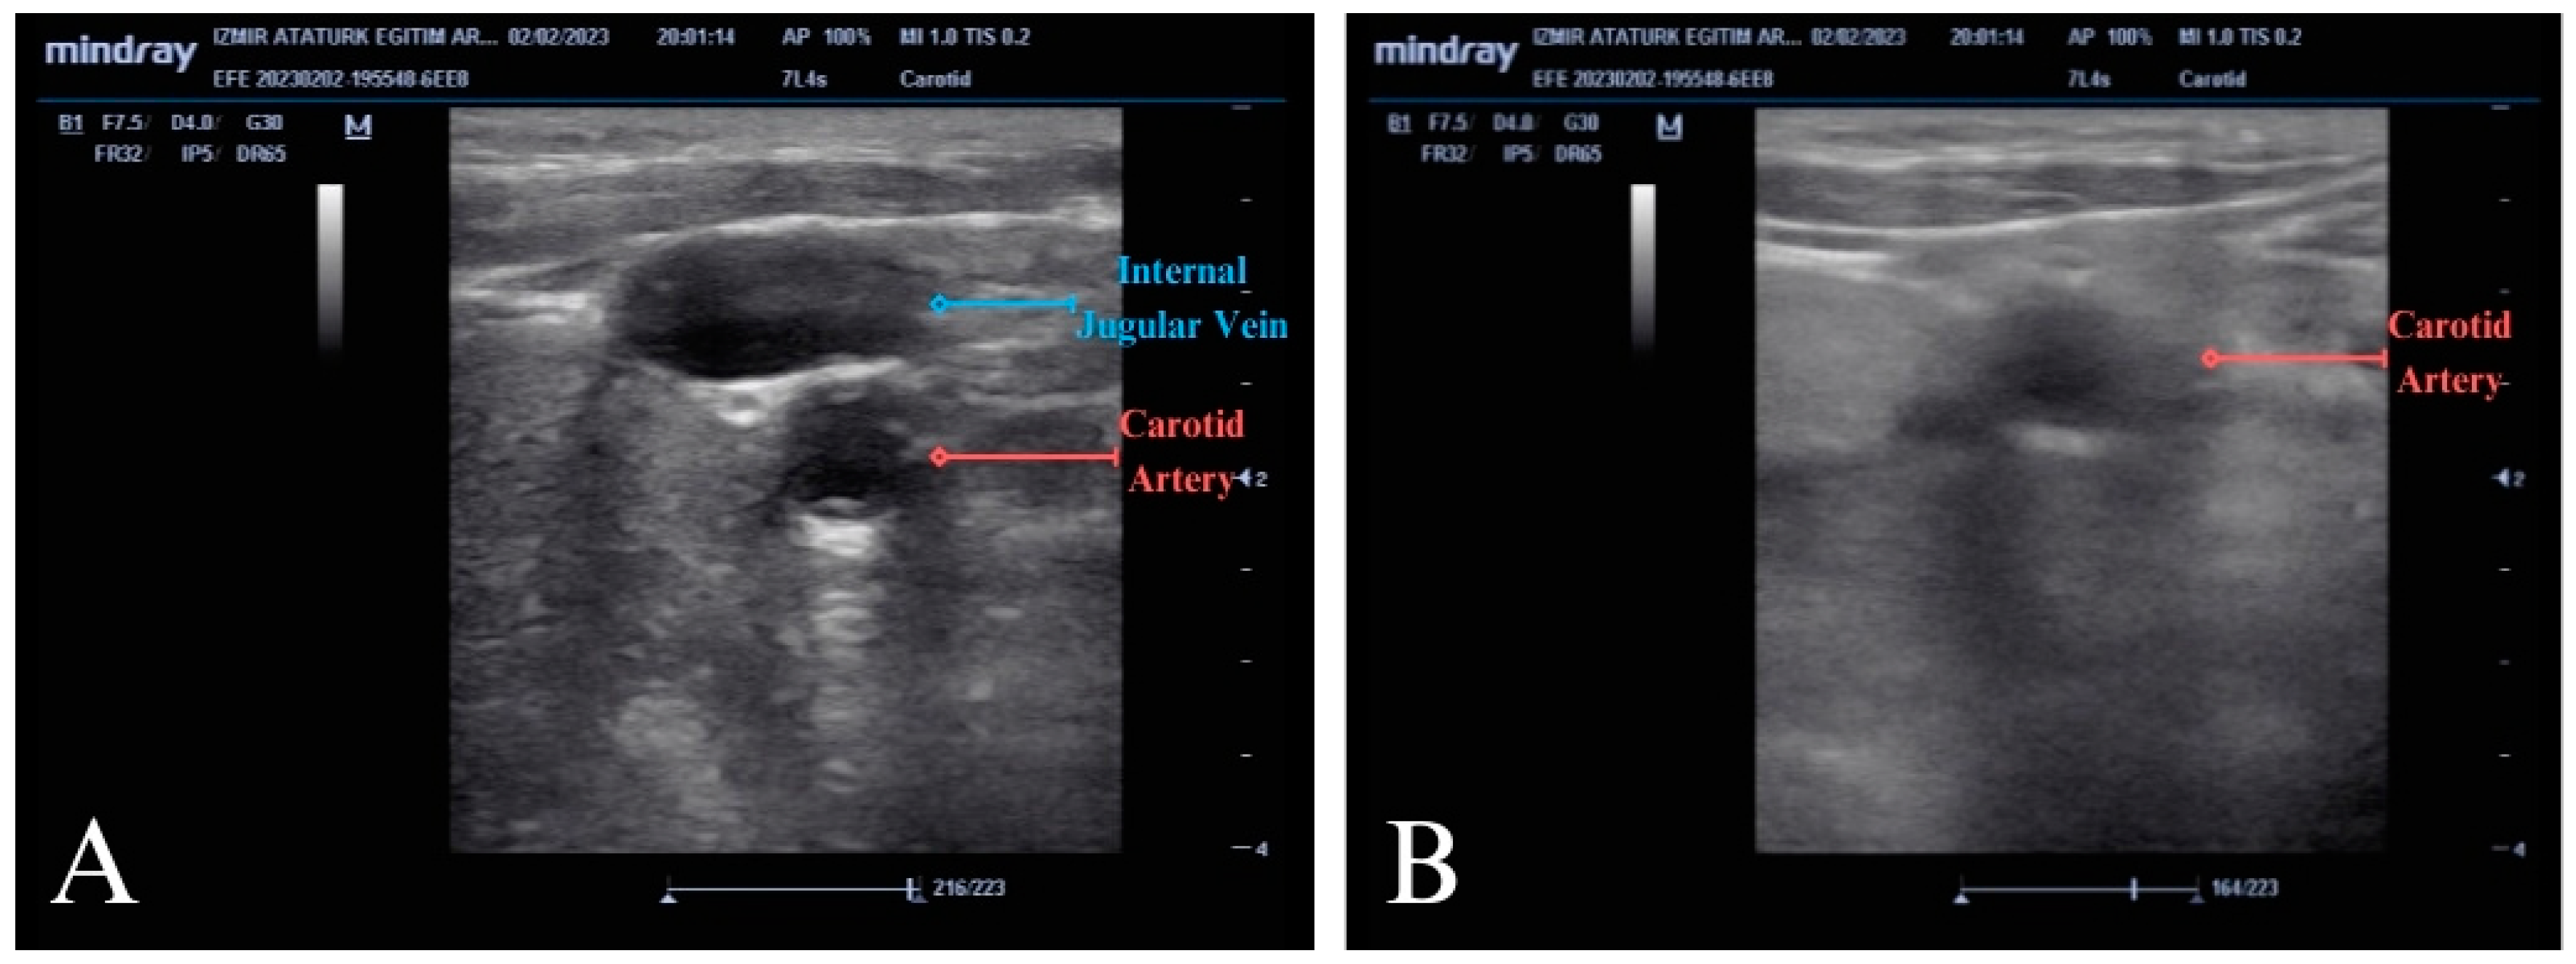

2.4. Measurement Method: POCUS-CAC

In this study, the protocol referred to as the POCUS-CAC protocol, previously described by Kang and colleagues, was applied [5]. In this method, during CPR, a linear probe was placed transversely between the two heads of the SCM muscle on the lateral side of the patient’s neck. After visualizing the internal jugular and carotid artery, pressure was applied with the probe until the internal jugular vein was fully compressed. Using this method, the carotid artery behaving like the vein and becoming fully compressed with the absence of pulsation was considered the absence of a pulse. The failure of the carotid artery to compress or the presence of any pulsation after compression was accepted as the presence of a pulse (ROSC) (Figure 2A,B; Video S1).

Figure 2. Ultrasound images demonstrating the POCUS-CAC method. (A) Internal jugular vein and carotid artery before applying compression. (B) The image of the carotid artery that does not collapse under POCUS-CAC during chest compressions (early detection of ROSC).